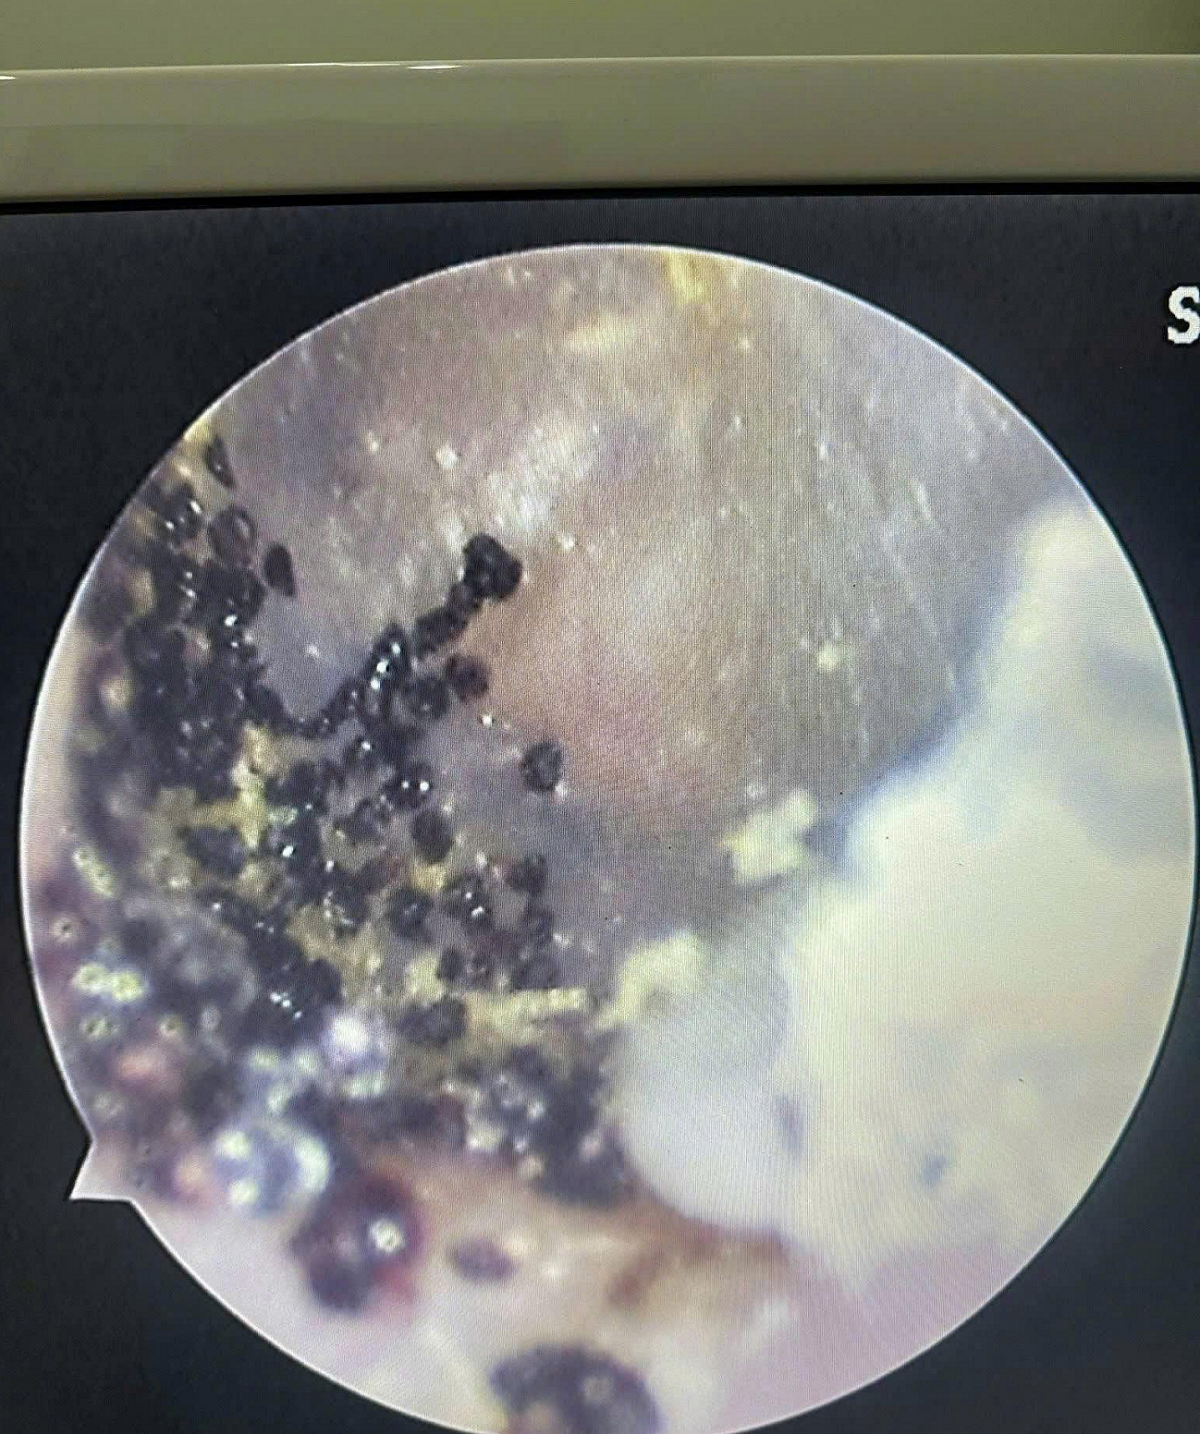

Hình ảnh ve và phân ve chó trong tai bệnh nhi. Ảnh: BVCC.

Qua kiểm tra, ê-kíp bác sĩ bệnh viện ghi nhận sát màng nhĩ tai trái của bệnh nhi có ve chó, kèm theo nhiều phân ve chó trong ống tai. Để đảm bảo an toàn và tránh nguy cơ tổn thương màng nhĩ cho bệnh nhi trong quá trình gắp dị vật, ê-kíp bác sĩ đã tiến hành gây mê ngắn, đồng thời thực hiện nội soi làm sạch, lấy toàn bộ ve và phân ve chó ra khỏi tai bệnh nhi. Sau thủ thuật, bệnh nhi tỉnh táo, tình trạng sức khỏe ổn định.